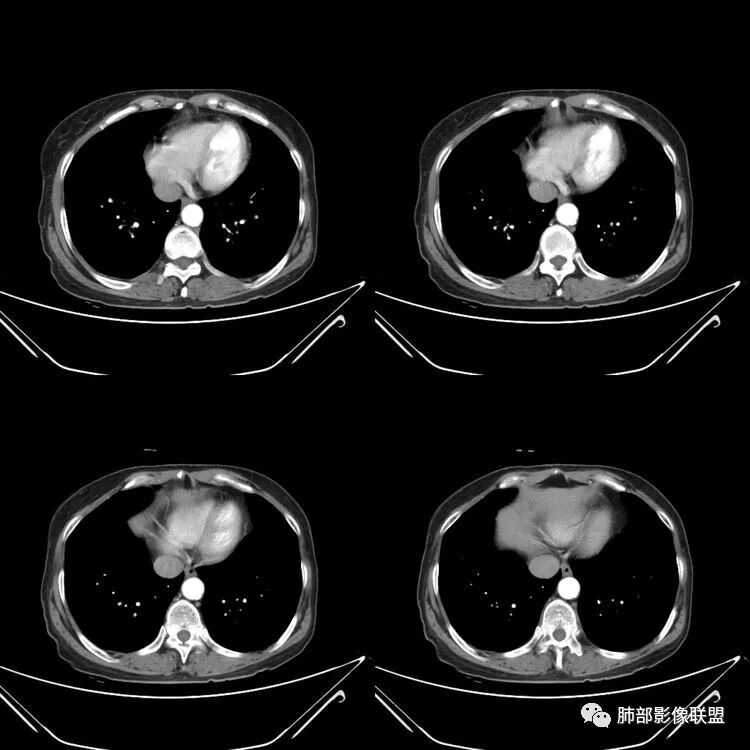

气管支气管弥漫性管壁增厚,膜部受累,疑似有局部钙化,管腔狭窄。考虑气管支气管淀粉样变。

气管支气管壁均匀增厚,膜部受累,未见腔内结节及腔外受累,支持淀粉样变性

老年人,感冒时痰中带血,影像表现气管支气管壁及后膜增厚,部分可见钙化,考虑支气管淀粉样变性,鉴别多发软骨炎,WG

老年男性,病程长,起病缓,有咳嗽,胸闷,痰血,气管支气管管壁弥漫性增厚明显,可见钙化,考虑淀粉样变。

主支气管壁增厚及壁内可见钙化影,累积支气管前壁及侧壁,双肺左右支气管壁也弥漫性增厚,左主支气管明显狭窄,病史10年,慢性病史,考虑支气管淀粉样变,鉴别复发性骨软骨炎(一般比较局限)

气管支气管壁弥漫性环周增厚,累及膜部,伴钙化,管腔变窄,考虑淀粉样变性

老年女性,慢性病程急性起病,主支气管及各级分支弥漫性不均匀性增厚,管壁钙化,管腔狭窄,累及膜部,考虑淀粉样变性,鉴别复发性多软骨炎,气管支气管骨化症,侵袭性曲霉菌病

气管及支气管管壁弥漫性增厚,累及膜部,局部伴钙化,管腔狭窄,局部管壁结节样增厚,不规则狭窄,考虑淀粉样变性,鉴别复发性多软骨炎,WG

患者,女,64岁,反复咳嗽、咳痰、胸闷10年,加重2周。气管支气管及两肺下叶 支气管弥漫性的环状增厚,管腔扩张,管腔感觉比较松弛。第一感觉,气管支气管淀粉样变。鉴别诊断,1、支气管内膜结核,肺内散在一些支气管的播散病灶,粟粒结节为主,形态比较单一。2、复发性的多软骨炎,就得了解一下其他部位,有没有多个部位的软骨炎。这个病人右侧胸廓缩小,升主动脉明显的扩张,其横径明显的超过了降主动脉。

气管支气管增厚,密度不均匀可见条状及斑点状高密度,未见强化,临床有咳血咳痰,支持支气管淀粉样变性,鉴别气管支气管骨化症

气管、支气管及分支支气管壁弥漫性环周增厚,局部管壁可见钙化,病史10年,慢性病史,考虑支气管淀粉样变。

气管及支气管弥漫性增厚,内缘模糊,部分管腔狭窄,软骨部及膜部均受累,考虑淀粉样变性

气管-支气管壁弥漫性增厚、膜部受累,见钙化,管腔变窄,考虑淀粉样变

南边:肺部有肺气肿支气管腔狭窄淀粉样变性?复发性多软骨炎?血管炎?慢支?结核?曲霉菌?南边:一般还是淀粉样变性与复发性多软骨炎鉴别其次就是支气管骨化症,但是骨化下朝上,且壁结节状钙化明显,本例不太支持。至于结核、曲霉菌?1.结核,一般不会这么广泛,支气管壁狭窄后扩张2.曲霉菌可以这么广泛,但是支气管壁管腔扩张,而且附近脂肪间隙有炎性反应,不太支持;3.血管炎,一般合并肺内有病灶,但是声带受累,放待排;4.软骨炎一般全身受累,例如耳廓等;而且膜部不受累,不太支持;倾向于淀粉样变性;淀粉分很多型,气管支气管是最常见的。尘缘:影像上生理性钙化与支气管骨化无法区别,镜检也不好鉴别,需要依赖活检,看粘膜中是否合并炎性改变(淋巴细胞,组织细胞等炎性细胞侵润)来鉴别Coke with ice:经常看到的这种是老年性肺改变,又称年龄相关肺改变。气管和支气管弥漫性软骨钙化,常见老年女性。尘缘:支气管骨化症很罕见的,所以绝大多数还是生理性钙化。对于老年人,无临床症状的钙化,还是基本上都是生理性钙化,无临床意义。大雄:如果管壁钙化伴明显增厚 影像还是提示一下建议支气管镜稳妥些

病理结果:肺淀粉样变